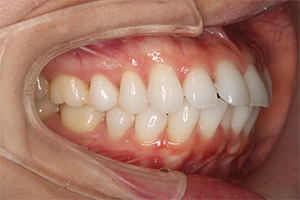

矯正治療のCASE 02

Before

After

- 主訴

- 上顎前歯が出ていて口が閉じにくい

- 治療内容

- 上顎前突・出っ歯の非抜歯による歯並び治療

- 治療費用

- 88万円~(税込)

- 治療期間

- 12ヶ月

【リスク・副作用】

歯の痛み、口内炎、歯磨きがしにくいことによるむし歯や歯周病のリスク、歯根吸収や歯の変色、後戻りなどの副作用があります。